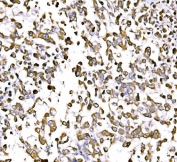

IHC staining of FFPE human rectal cancer tissue with GGA3 antibody. HIER: boil tissue sections in pH8 EDTA for 20 min and allow to cool before testing.

IHC staining of FFPE human pancreatic cancer tissue with GGA3 antibody. HIER: boil tissue sections in pH8 EDTA for 20 min and allow to cool before testing.

IHC staining of FFPE human liver cancer tissue with GGA3 antibody. HIER: boil tissue sections in pH8 EDTA for 20 min and allow to cool before testing.